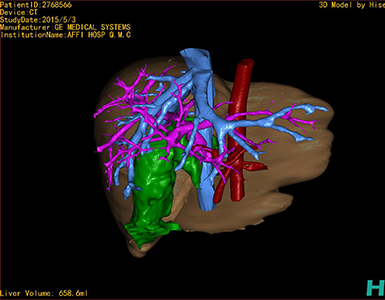

CT结果输入海信CAS系统后行3D重建及手术规划后,于2015-5-6全麻下行“胆总管囊肿切除+胆囊切除+胆总管-空肠吻合术”手术治疗:

术前三维重建及手术方案设计:

将0.625mm双源薄层CT资料的静脉期和动脉期Dicom格式文件导入海信CAS系统。

通过调节窗宽窗位调整CT序号,对肝实质,胆囊,下腔静脉,肿瘤,肝动脉、门静脉及肝静脉等进行三维重建;系统自动计算肝脏体积。

术前手术方案的规划。

完善术前准备后,选择右上腹纵口进入腹腔。结合海信CAS术前规划方案,探查见:胆总管3×2cm大小,胆囊管迂曲,长约10cm。剥离、切除胆囊,游离胆总管,将之横断:①近端即肝总管,剪裁后被吻合用;②远端游离切除囊肿内壁,直至胆总管开口于十二指肠处,冲洗后予以结扎缝扎。距treits韧带20cm处横断空肠:①近端与其远端25cm处的空肠侧壁行端侧双层吻合,吻合口通畅;②远端断端封闭,其侧壁剪开,并经横结肠后提至肝门处,与剪裁的肝总管行端侧双层吻合。缝合修补胆囊床及系膜裂孔,肝门部放置橡胶引流管一根。温盐水冲洗腹腔。检查无活动性出血,清点纱布器械无误,依次缝合腹壁各层。术后胆囊标本家属过目,送检病理。手术时手术者可开启Hisense CAS系统手势控制功能,对胆囊周围血管、组织的解剖结构进行实时、全方观察、评估,起到术中导航作用。

术前三维重建:

重建图片